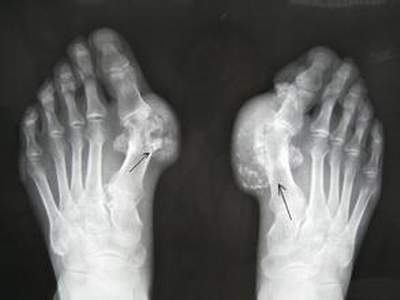

痛風(fēng)治療的關(guān)鍵就是合理有效的控制尿酸的水平,因此需要長期服用控制尿酸的藥物,優(yōu)立通就是近年來被廣泛引用于痛風(fēng)臨床治療的藥物,那么優(yōu)立通治療痛風(fēng)的作用怎么樣?優(yōu)立通適用于哪類患者服用?

優(yōu)立通是從根源上來抑制尿酸產(chǎn)生的,能有效減少痛風(fēng)并發(fā)癥的產(chǎn)生,尤其是在抑制高尿酸癥對(duì)腎臟功能方面的損害方面作用很大。

優(yōu)立通適合痛風(fēng)的間歇期和慢性期服用,適用于痛風(fēng)患者高尿酸血癥的長期治療。不推薦用于沒有臨床癥狀高尿酸血癥的患者。口服推薦劑量為40mg80mg,每日一次。推薦本品的起始劑量為40mg,每日一次。給藥劑量40mg,持續(xù)兩周后,對(duì)血清尿酸水平(sUA)仍高于6 mg/dl的患者,推薦給藥劑量80mg

給藥本品時(shí)無需考慮食物或抗酸劑的影響。特殊人群輕或中度腎功能損傷患者服用本品時(shí)不必調(diào)整劑量。輕中度肝功能損傷患者服用本品無需劑量調(diào)整。對(duì)嚴(yán)重肝功能損傷患者使用本品尚無研究,因此給藥本品應(yīng)謹(jǐn)慎。尿酸水平使用本品治療2周后即可進(jìn)行血清尿酸的再檢驗(yàn)。

優(yōu)立通禁用于正在接受硫唑嘌呤、巰嘌呤治療的患者。開始應(yīng)用優(yōu)立通治療后,可觀察到痛風(fēng)發(fā)作增加。這是由于變化的血清尿酸水平減少導(dǎo)致沉積的尿酸鹽活動(dòng)引起的。為預(yù)防給藥優(yōu)立通時(shí)發(fā)生痛風(fēng)發(fā)作,推薦同時(shí)給藥非甾體抗炎藥或秋水仙堿。

現(xiàn)有的臨床證據(jù)表明,優(yōu)立通在短,中,遠(yuǎn)期治療方面的效果是優(yōu)于別嘌醇的。從國外研發(fā)開始至今歷時(shí)近十年積累數(shù)據(jù)表明是長期可靠有效,而且作用機(jī)制靶向單一、準(zhǔn)確,副作用少。并且是目前唯一一個(gè)治療效果不受高脂飲食影響的痛風(fēng)治療藥,符合現(xiàn)代社會(huì)相當(dāng)人群生活習(xí)慣。